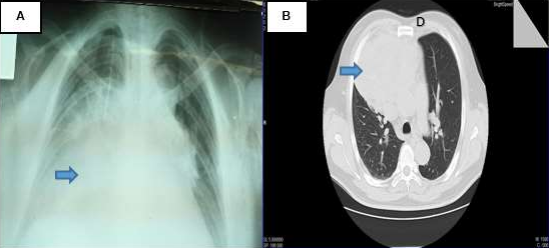

In December, after a Multidisciplinary Meeting of the Thorax Comitee, it was decided to perform a tumor cytoreduction, which revealed a large, highly vascularized thymic tumor adherent to the heart and large vessels. The anatomopathological result was papillary adenocarcinoma of thymus with positive immunohistochemistry for Ki-67 (10%) and pancytokeratin, and negative for p53, TTF-1. CD45, CK7 and CK20 (Figure 3B). During surgery, the patient presented hemodynamic instability and respiratory failure, so partial surgery was performed and he was transferred to Critical Care Unit, presenting favorable evolution. The patient was reevaluated after surgery (February 2017) by control tomographic scan (Figure 4) and evidencied disease progression, an anterior mediastinal mass measuring 140mm x 130mm x 115mm, associated to adjacent lymph node conglomerates, mild pleural effusion, retroperitoneal lymph node conglomerates, and lytic lesions in the cranial calotte, costal arches and D8.

Figure 4. Postoperatory tomography scan (02/28/17). There is evidence of (A) new lytic lesion in cranial calotte, (B) anterior mediastinal mass of 140mm x130mm x 115mm that infiltrate adjacent structures and associated with lymph node conglomerates and right mild pleural effusion, and (C) lytic lesions in costals arches and vertebrals bodies.